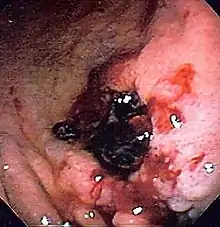

Endoscopic still of esophageal ulcers seen after banding of esophageal varices, at time of esophagogastroduodenoscopy | |

- Treatment (banding/sclerotherapy) of esophageal varices